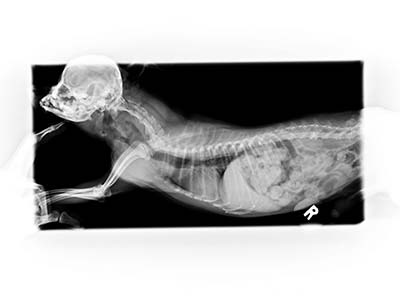

本病歷的小貓咪就是趁媽媽不在偷跑去玩線,媽媽回來後發現小貓一直乾嘔而帶來醫院就診,在X光下赫然發現胃裡有一根針!和醫師討論後手術利弊後,決定使用可以馬上回家且無創的內視鏡手術將異物取出。麻醉甦醒後,小貓很快恢復了精神活力,好像什麼都沒發生過,開開心心的回家了。

X光可以看到胃中有一根針

仰照也可以看到針的位置